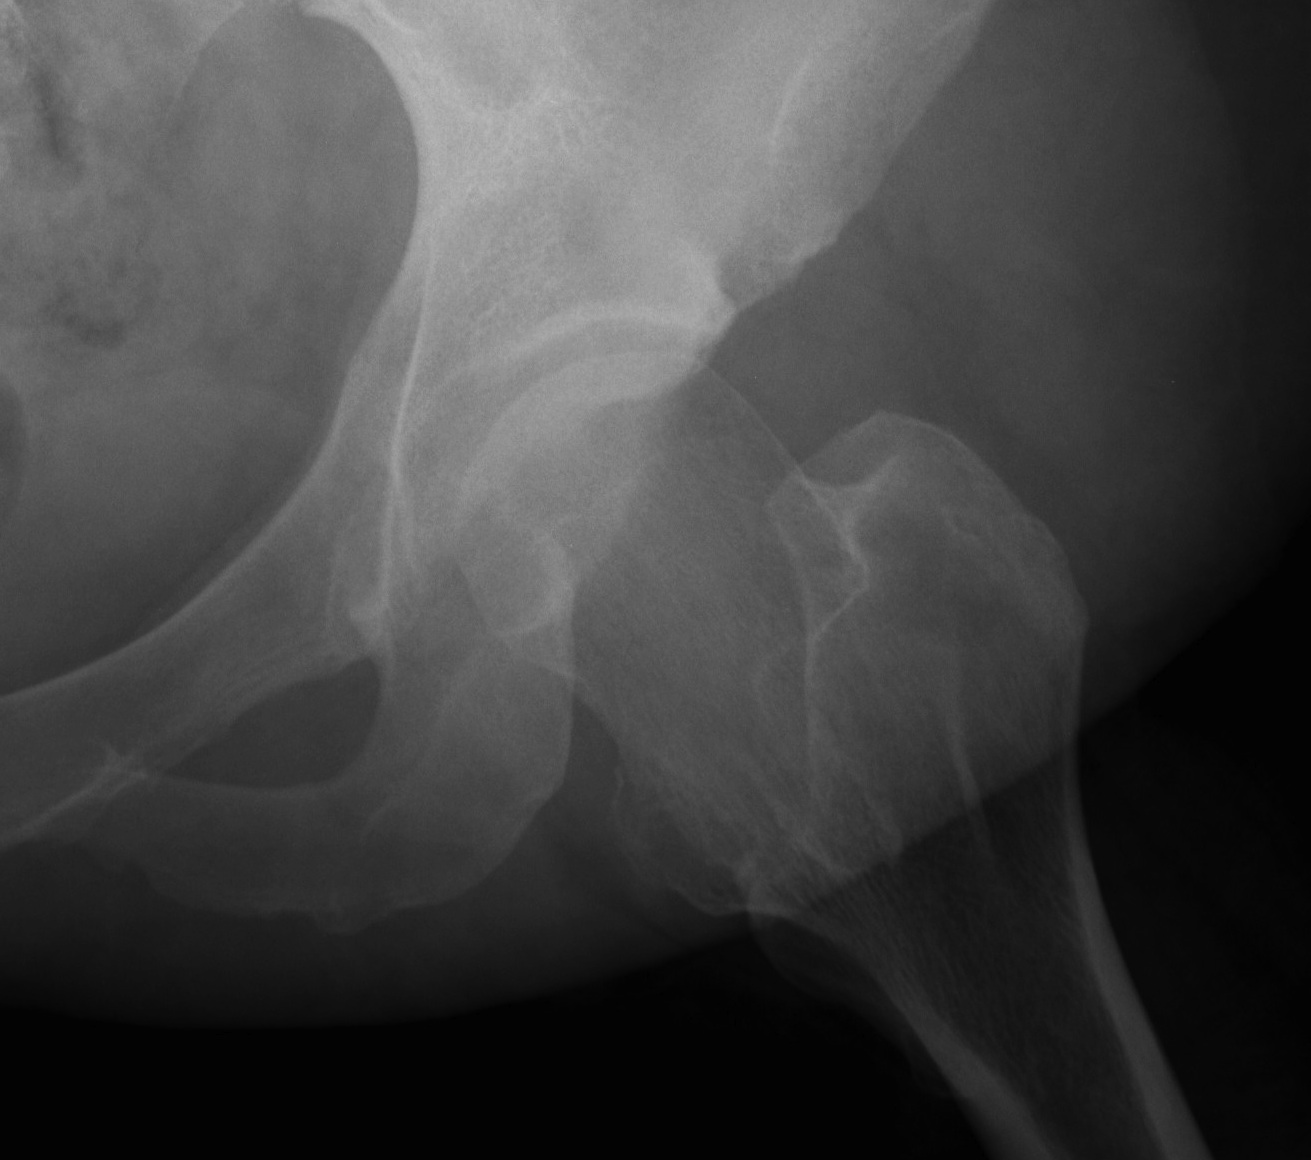

4. Tonnis

Concept

- Salter osteotomy plus pubis and ischial between ischial tuberosity and acetabulum

- get better or easier correction because osteotomies are closer to acetabulum

5. Ganz

- periacetabular osteotomy

- posterior column left intact for stability

Indications

- older adolescent and adults

- with residual dysplasia

Advantage

- excellent rotation with medialisation

- increase CE 27o

Technique

- isolate acetabulum from ileum / ischium via 3 part osteotomy

- separate superior rami osteotomy at base